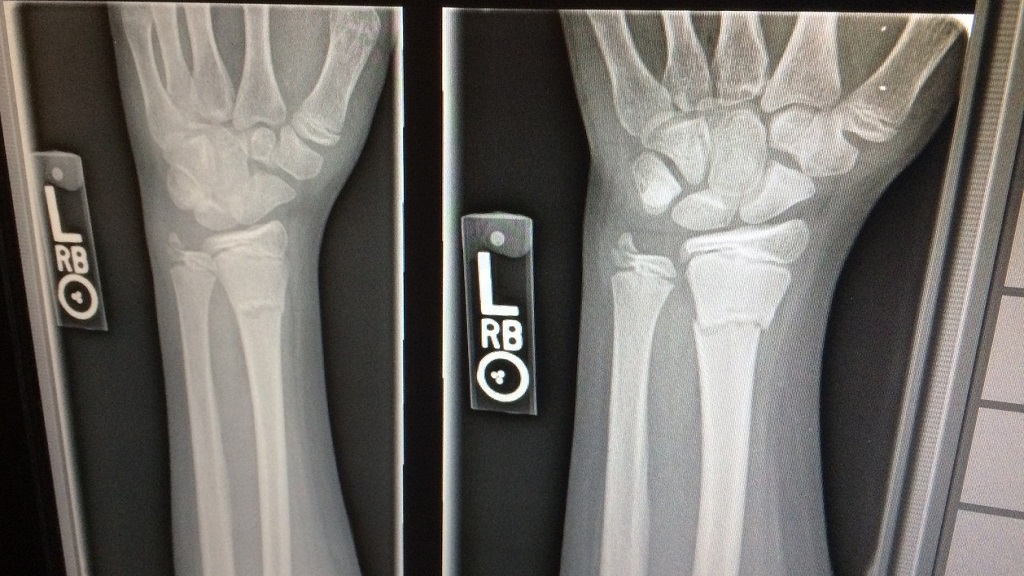

A través de una unidad móvil medicalizada con equipos de radiólogos altamente especializados, la compañía española facilita la realización de ecografías y radiografías de manera más ágil y cómoda, ya sean de carácter urgentes o programadas. Comitas e-health utiliza equipos de última generación, datos encriptados y una gran novedad, que las pruebas pueden ser entregadas al paciente o ser enviadas a la clínica o médico que siga su historial.

Las unidades móviles han sido diseñadas específicamente para su función y disponen de la más avanzada de tecnología en diagnóstico por imagen que permite cubrir todas las necesidades radiológicas, en un espacio acogedor y funcional que incluye un vestuario para el paciente.